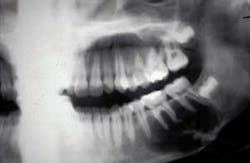

In order to establish a permanent record for Jonathan, you proceed to first examine his mouth and take a full-mouth set of radiographs. The intraoral exam results in an area of concern for you since the right apical areas of the molars appear to be somewhat elevated. The radiographs that you subsequently take reveal a true area of concern in the mandible.

The related radiograph depicts a radiolucent lesion around the mandibular molar teeth extending from the second premolar to the distal of the second molar. The border of the radiolucent lesion may be described as scalloped and reaching to the inferior border of the mandible. The scalloping in between the roots follows the nature of the traumatic bone cyst.